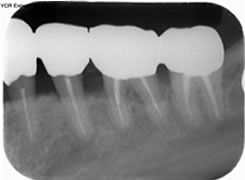

治療の特徴(患者I様)

初診時においては物を咬むと違和感が強く歯周外科処置を行いました。

骨のラインが部分的に増え、平坦にきれいに治っています。

2019年5月20日現在